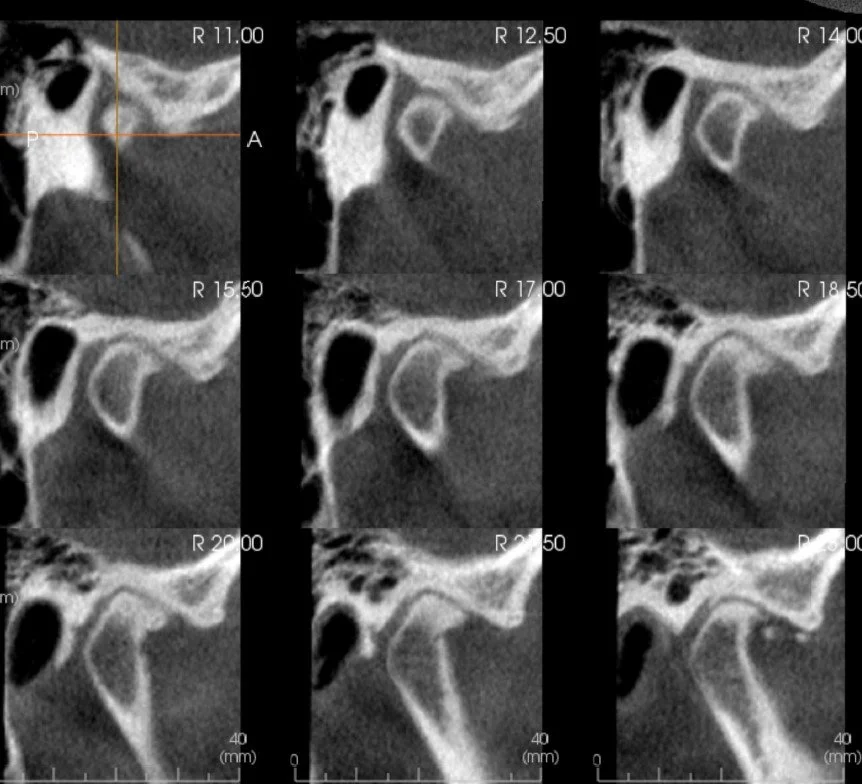

What is a Cone-Beam Computed Tomography or CBCT? Is it a CT scan?

Cone-beam Computed Tomography, or CBCT for short, is a type of low-dose CT scan that allows us to visualize your teeth, jaws, TM joints and airways accurately in 3-dimensions. This advanced imaging technology has markedly improved our ability to diagnose and treat several dental and jaw problems. Dental CBCT examinations expose you to considerably less radiation than the CT scans made in hospital settings.